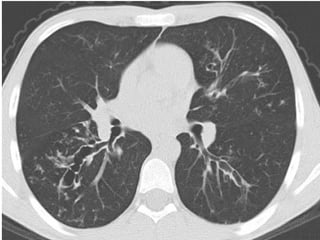

 TDM thoracique :

   Examen de référence pour mev des DDB proximales

(critère majeur de Dic) et des impactions mucoides .

   Permet de voir les images associées : infiltrats

labiles, atélectasies, aspect d’emphysème.

   Plus sensible et plus précoce pour Dic des fibroses

pulmonaires.

Bronchectasies centrales

Impactions mucoides

DDB cylindriques et kystiques proximales prédominant aux

lobes sup, avec trbles ventilatoires et bronchomucocèles.